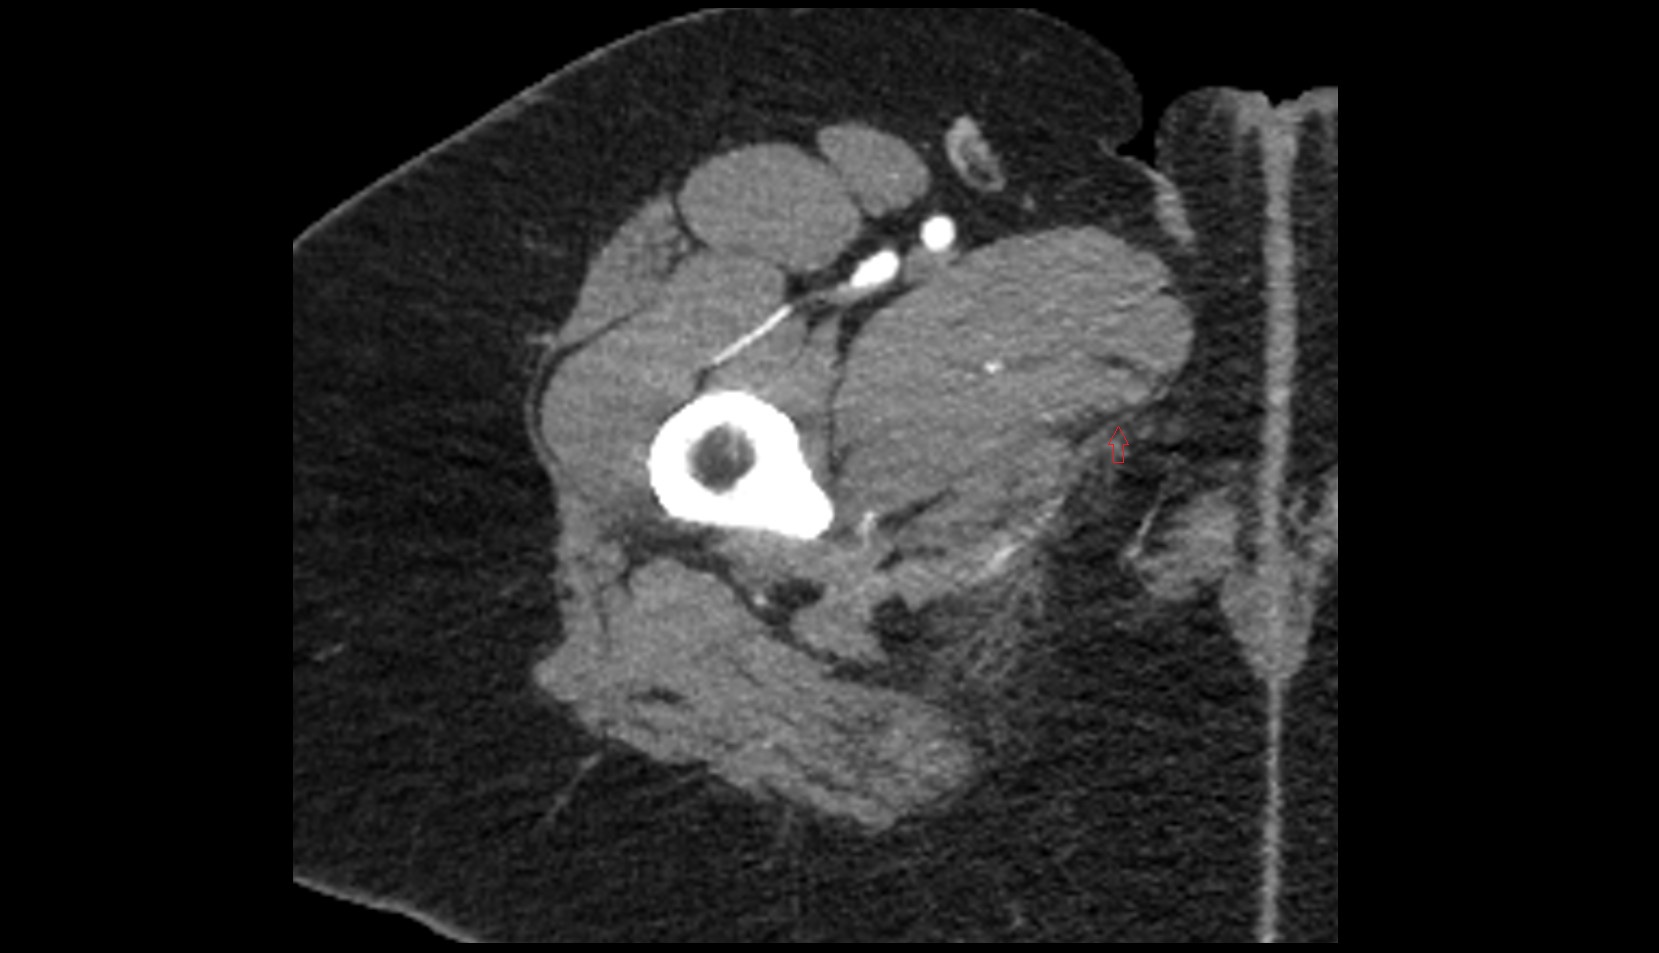

- Head of femur

- Neck of femur

- Acetabular margin (Acetabular rim)

- Acetabulum

- Anterior acetabular wall

- Posterior acetabular wall

- Greater trochanter

- Lesser trochanter

- Acetabular labrum

- Ischiofemoral ligament

- Transverse acetabular ligament

- Articular capsule of hip joint